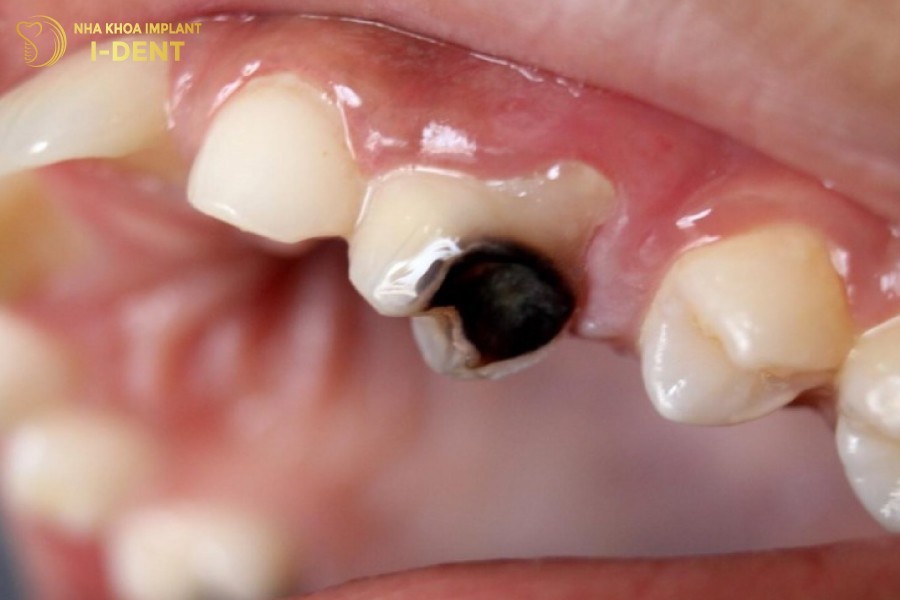

Trường hợp sâu răng ở mức độ nghiêm trọng, viêm nhiễm đã lan rộng mất gần hết răng và răng không thể phục hồi, các bác sĩ sẽ chỉ định nhổ răng sâu để ngăn ngừa các biến chứng nguy hiểm. Sau đó, bệnh nhân nên cấy ghép Implant để phục hình răng mất, giúp duy trì chức năng ăn nhai và thẩm mỹ của hàm răng.

Răng sâu nặng không thể phục hồi thì nên nhổ và cấy ghép Implant